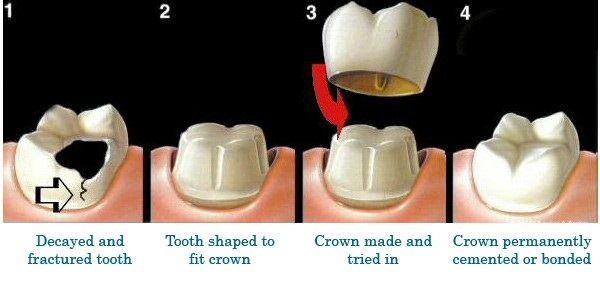

In the long term, implants are aesthetic, functional and comfortable. Gums and bone can recede around a fixed bridge or removable partial denture, leaving a visible defect. Resorbed bone beneath bridges or removable partial dentures can lead to a collapsed, unattractive smile. The cement holding bridges in place can wash out, allowing bacteria to decay teeth that anchor the bridge. In addition, removable partial dentures can move around in the mouth and reduce your ability to eat certain foods.